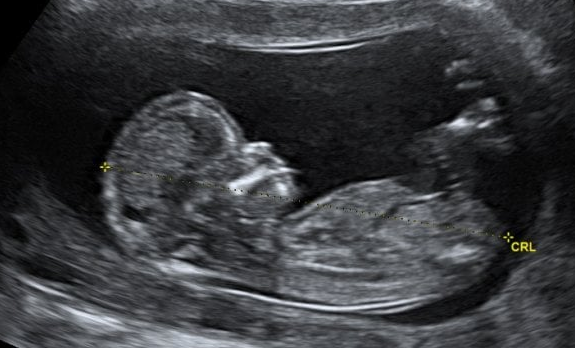

Este estudio puede hacerse desde el segundo mes de embarazo, pero es mucho más recomendable entre el quinto y séptimo mes para que se obtenga una imagen más clara del bebé.

Recuerda que es posible practicarlo en cualquier momento del embarazo, que facilita saber el sexo del bebé y que te dejará ver su anatomía muy claramente.